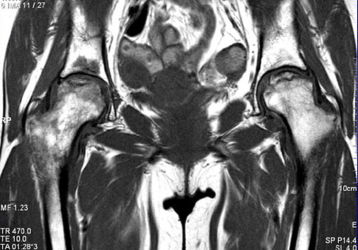

Что показывает МРТ тазобедренного сустава и всегда ли нужно его делать?

Магнитная томография тазобедренного сустава: показания и противопоказания к проведению. Что показывает обследование. Как проводится.